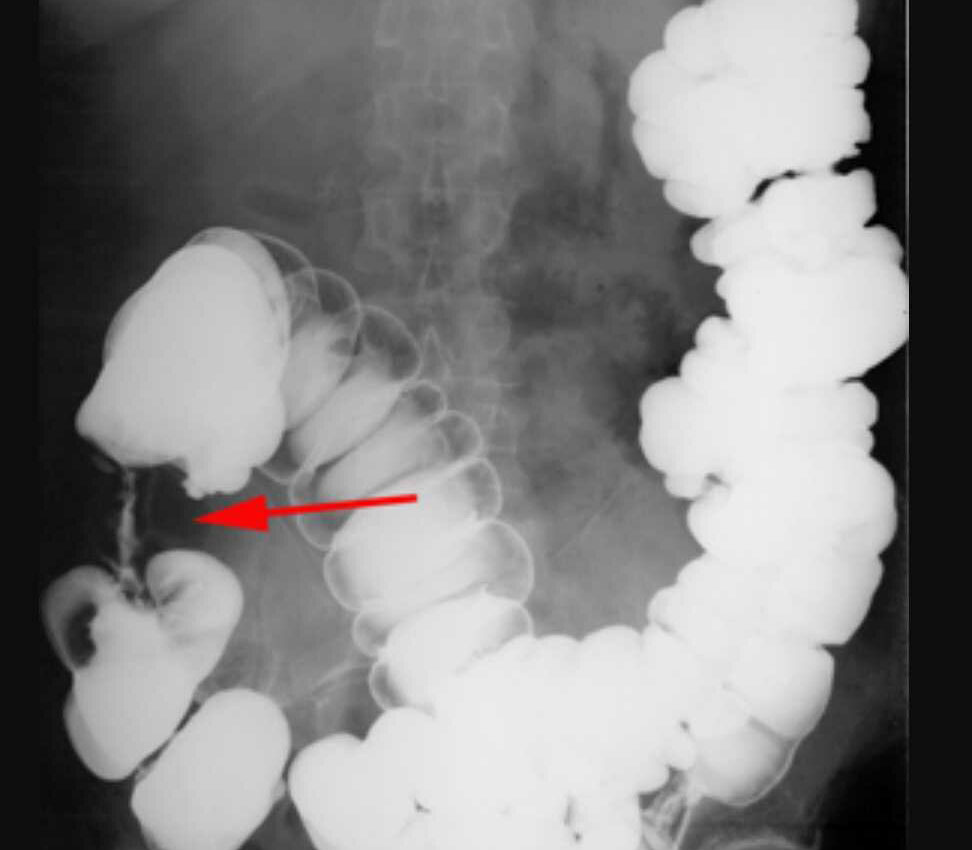

Ирригоскопия кишечника. Сужение просвета кишки в месте нахождения опухоли.

Колоноскопия была проведена в течение недели. Эндоскопист обнаружил в восходящем отделе ободочной кишки объемное образование, суживающее просвет кишки. Биопсия подтвердила диагноз: аденокарцинома толстой кишки. Дальнейшее обследование (КТ органов брюшной полости и грудной клетки) позволило установить стадию заболевания и спланировать лечение.